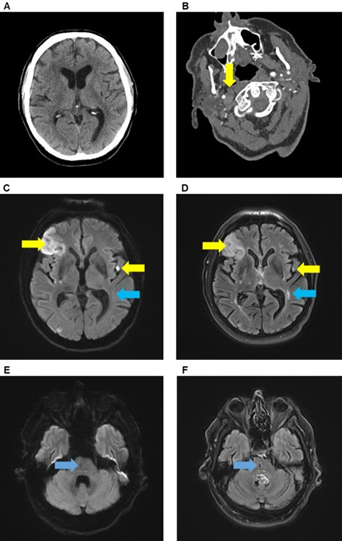

Immediate cranial computed tomography (CT) scan did not show any brain infarction (Figure 1A). CT angiography (CTA) revealed an occlusion of the right common carotid artery (ACC) as well as the proximal right internal carotid artery (ACI) (Figure 1B). Acute stroke treatment included systemic thrombolysis (using 81 mg alteplase) and endovascular treatment with percutaneous transluminal angioplasty and stenting of the right ACC and ACI. The following day, magnetic resonance imaging (MRI) showed an embolic pattern of bihemispheric acute, subacute ischemic lesions and a prior pontine lacunar lesion (Figure 1C-F). The patient was treated with aspirin (100 mg/d) and clopidogrel (75 mg/d) starting 24 hours after thrombolysis.

Figure 1: Brain imaging. CT and CT-angiography demonstrating no early signs of ischemic stroke (A) but an occlusion of right common carotid artery (B, yellow arrow) and internal carotid artery. Brain MRI showed multiple new (yellow arrows) and old lesions (blue arrow) in the territory of the left and right medial cerebral artery in DWI (C) and FLAIR sequence (D) as well as a previous lacunar lesion in the right pons (blue arrow) in DWI (E) and FLAIR sequence (F).